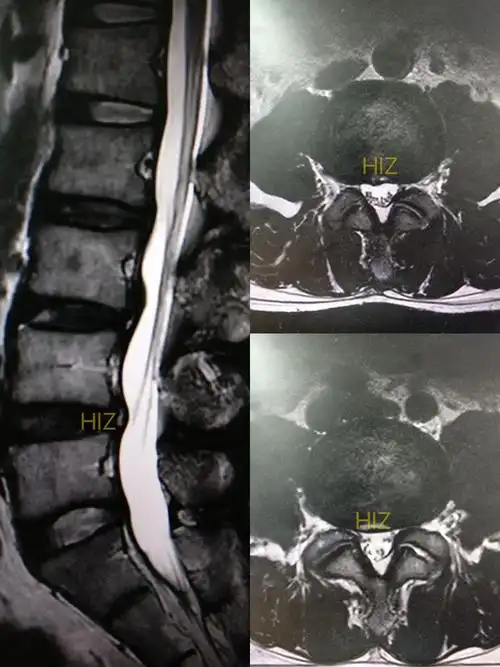

腰45极外侧突出?

l4/5椎间盘膨出,突出,甚至脱出,钙化!